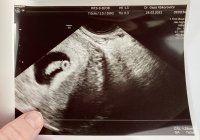

han tok nok flere målinger som i gjennomsnitt gav 6+3, mens denne ene målingen kanskje viste tilsvarende 6+6. I de fleste tilfeller er det uansett menstermin som "teller" frem til ordinær UL

Fikk høre hjertet også- veldig deilig!